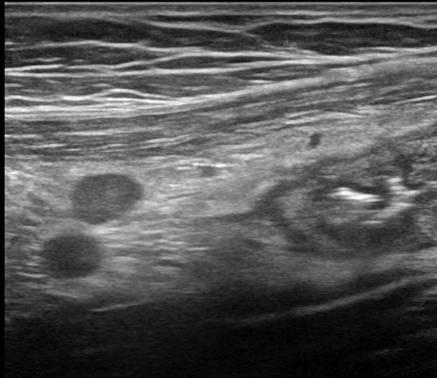

Viêm ruột

» Thông tin: Nữ giới – 18 tuổi.

» Lâm sàng: Tiêu chảy.